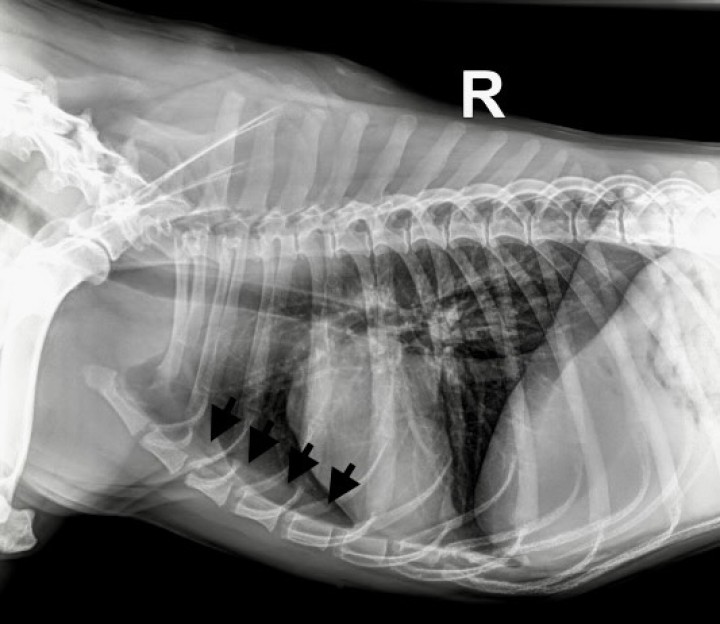

1. Tomografia computarizada (TC): se realizó un estudio de cuerpo completo, incluyendo imágenes pre y postcontraste intravenoso, procesadas con algoritmo de tejidos blandos y de pulmón, con espesor de cortes de 1 mm, donde se evidenció la presencia de una masa en el mediastino craneal, extendiéndose hacia el hemitórax izquierdo, con unas medidas de 16,6 cm de largo por 7 cm de ancho y 8,7 cm de alto. La lesión presentaba márgenes bien definidos, atenuación de tejidos blandos, realce leve y homogéneo. La lesión causaba un desplazamiento dorsolateral hacia la derecha de los principales vasos del mediastino craneal, y compresión moderada/severa de la vena cava craneal. La lesión se encontraba en contacto con el aspecto craneolateral izquierdo del corazón, que aparecía desplazado caudalmente y hacia el lado derecho por la masa mediastínica. Era también visible la retracción de los lóbulos pulmonares craneales, más evidente en el lado izquierdo, debido a la expansión de la lesión mediastínica (Fig. 2).

Imágenes de TC postcontraste en ventana de tejido blando de la masa en mediastino craneal, extendiéndose hacia el lado izquierdo del tórax. (A) Plano sagital. (B) Plano axial. (C) Plano coronal. Nótese el corazón desplazado en dirección caudal y hacia el lado derecho. M: masa; C: corazón.